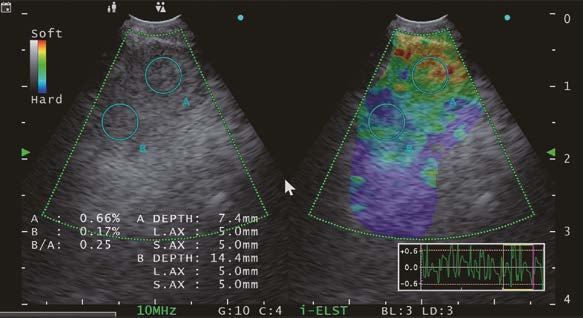

ELST Mode (i-ELST)

Case) 70 years old male patient presented himself 6 years and 10 months after thoracoscopic resection surgery for lung cancer in the right lower lobe.

A nodule in the left lung and an enlarged mediastinal lymph node was identified at a different hospital. The patient was subsequently referred to our hospital for further evaluation and management.

In this case, blood flow was observed in the upper right of the lymph node where the needle would pass through, so it was necessary to avoid this area when puncturing the lymph node.

The selection of the puncture site was determined by using the ELST mode. The EU-ME3 with its newly equipped “i-ELST function”, enables to display stable ELST images even with minute vibrations. The ELST images were green at the center of the lymph node and predominantly blue at the margins of the lymph node.

It has been reported that a combination of ELST and B-mode images is useful for identifying the most suspected site of the lymph node when performing EBUS-TBNA.*

As described above, we were able to collect viable tumor cells and the core by adjusting the puncture site and puncturing the node referring to the ELST mode images.

Small cell carcinoma was suspected by rapid on-site cytologic evaluation during EBUS-TBNA and immediately confirmed by a pathologist. We determined pleural dissemination and diagnosed stage IV small cell carcinoma. Chemotherapy with CBDCA + VP-16 + Durvalumab was started.

Moreover, the utilization of Elastography mode during procedures or playback measurements with recorded Elastography mode images from the EU-ME3’s internal memory allows for the collection of Strain Ratio* and Strain Histogram**. As previously reported2),3), Elastography offers essential parameter data to assess tissue stiffness (elasticity) in a specific region of interest (ROI). In my view, the integration of i- Elastography with convex-probe endobronchial ultrasound could prove to be a valuable tool for predicting and precisely locating metastatic lymph nodes during EBUS-TBNA in the future.

2) Rozman A, et al. Endobronchial ultrasound elastography strain ratio for mediastinal lymph node diagnosis. Radiol Oncol. 2015;49(4):334-40.

3) Nakajima T, et al. Elastography for Predicting and Localizing Nodal Metastases during Endobronchial Ultrasound. Respiration. 2015;90(6):499-506.

*The Strain ratio is calculated as the ratio between the strain in the reference tissue of the region of interest and the strain within the target lesion of the ROI. The higher the strain ratio, the stiffer the lesion.

**In strain histogram analysis, lesion stiffness is calculated as mean pixel color values of a single ROI within the target lesion. Values range from 0 to 255 (from blue over green to red). Increasing lesion stiffness causes a decrease in mean histogram values.